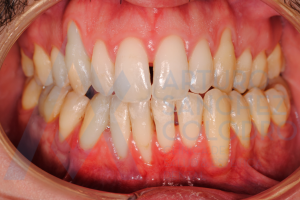

Hoy queremos compartir con vosotros el caso de éxito de un paciente que presentaba recesiones múltiples.

Estas son las imágenes obtenidas de exploración intraoral inicial: